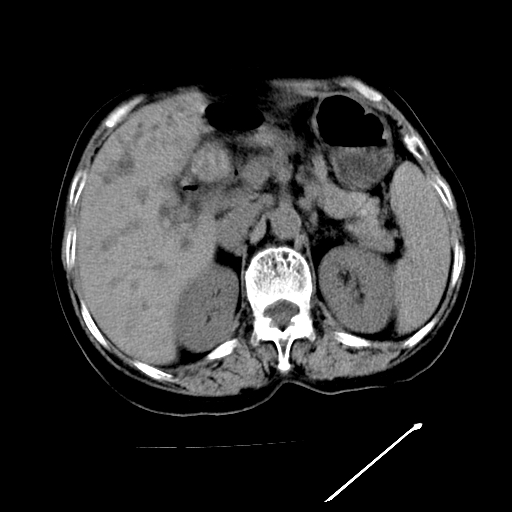

以下是引用随光逐影在2009-4-7 8:21:00的发言:[br]肝内外胆管多发性结石并肝内外胆管扩张;胆系感染。